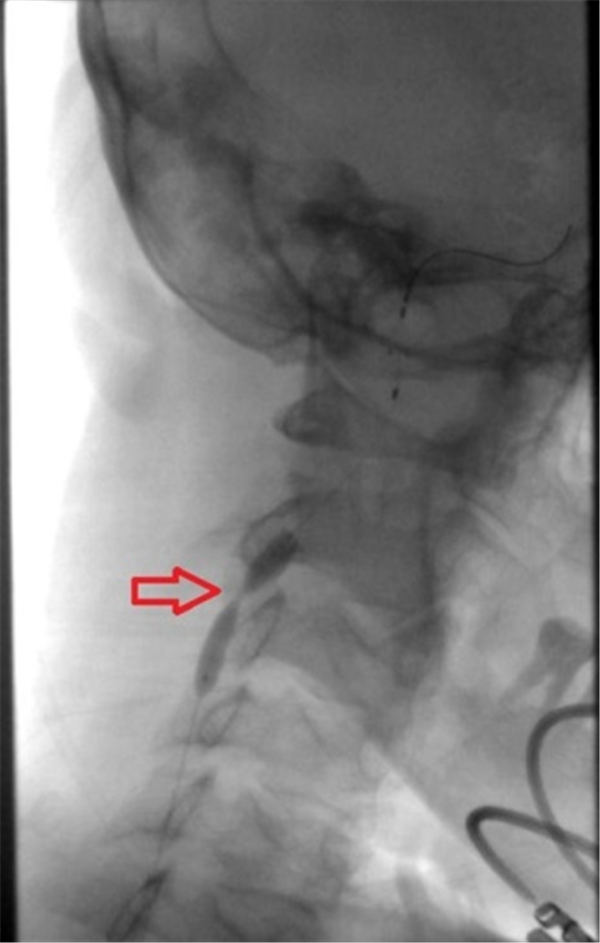

之后用球囊扩张右侧颈内动脉(上图红色箭头所示为狭窄部位)。

球囊完全扩张后,可见狭窄部位血流通畅(上图红色箭头所指)。